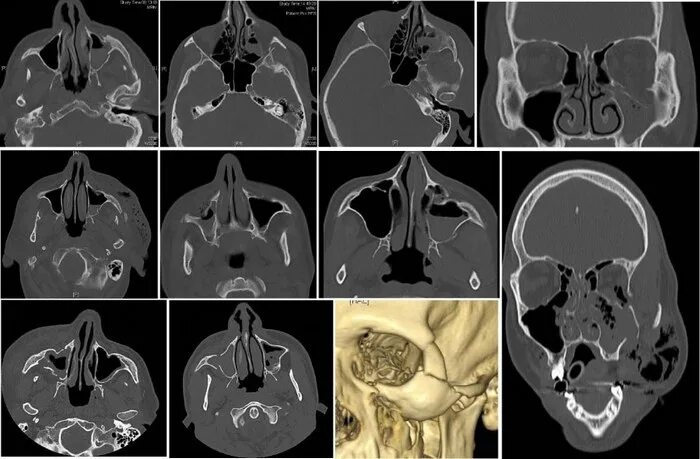

Перелом стенки левой орбиты